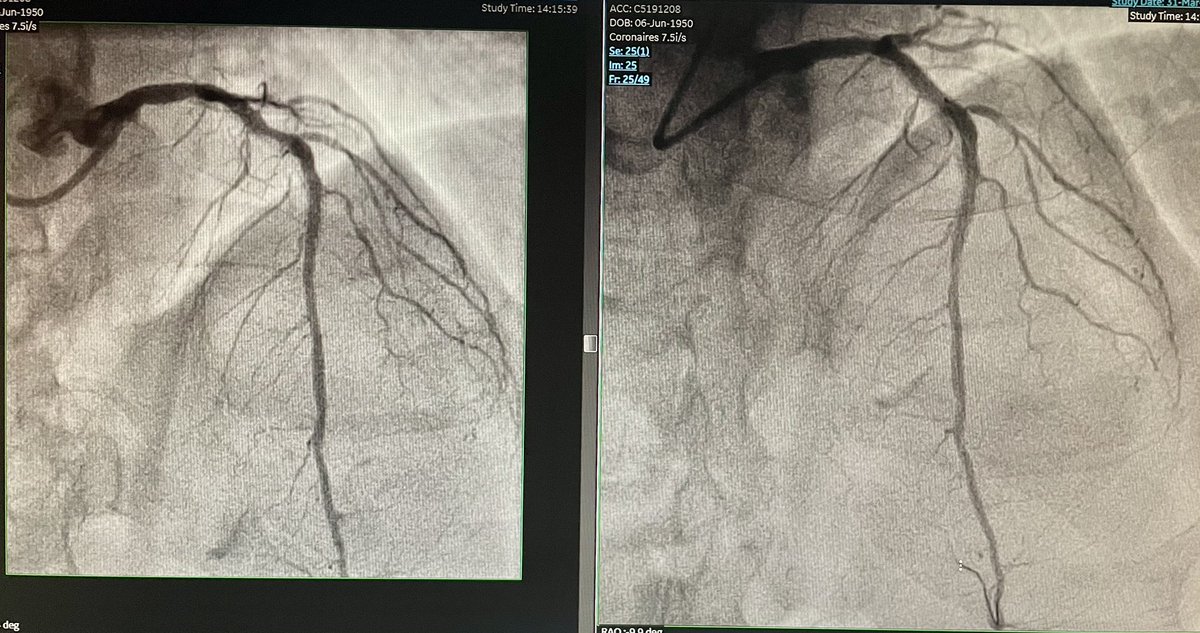

Glad for our first session of 3 Coronary Sinus Reducer cases with Pierre Barnay and Sébastien Armero at #HopitalEuropeen Marseille.

Thanks to @fra_giannini1 (our proctor) and @Neovasc team.